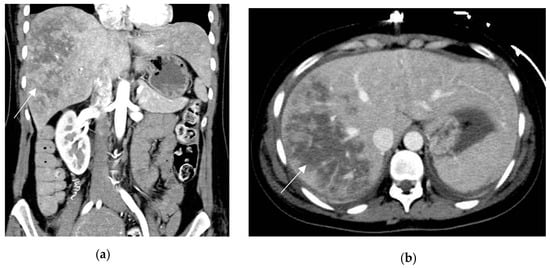

Liver infarction can be undetectable through US or appear as peripheral geographic hypoechoic bands [43]. MRI can show corresponding parenchymal signal changes, such as hyperintense on T2WI and hypointense on T1WI, according to the degree of the necrosis [44]. CT shows peripheral, ill-defined and wedge-shaped areas of decreased or absent enhancement, without mass effect (Figure 4); enhanced intrahepatic vessels are visible within the ischemic areas [42,45].

Figure 4.

HELLP syndrome in a 29-year-old patient with severe abdominal pain, onset 72 h after delivery. Prepartum hypertension, proteinuria and derangement of LFTs. Coronal and axial contrast-enhanced CT (a,b) show large and markedly hypoattenuating intrahepatic areas consistent with liver infarction (arrows). Lack of active arterial hemorrhage or intrabdominal bleeding.